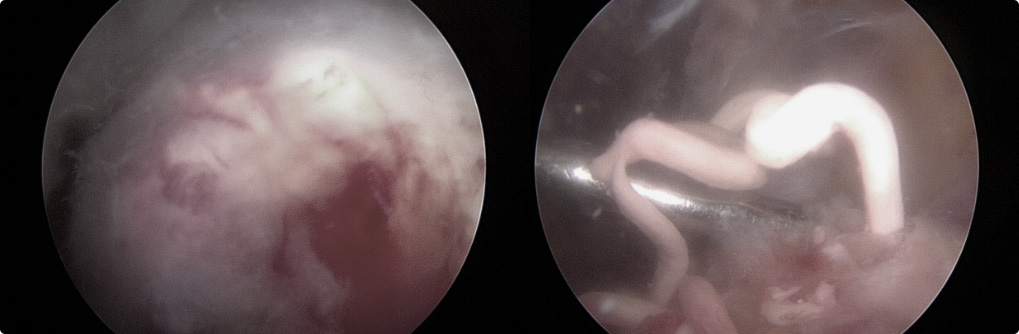

관절 내시경을 통한

석회제거술

내시경을 통하여 석회를 직접 보며,

힘줄 손상을 최소화시켜 석회 및 염증을 제거합니다.